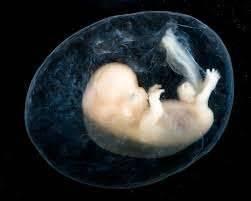

من الإخصاب إلى الولادة، يتطلب الحمل عددًا من الخطوات في جسم المرأة. إحدى هذه الخطوات هي عندما تسافر البيضة المخصبة إلى الرحم لتثبيتها. في حالة الحمل خارج الرحم، لا ترتبط البويضة المخصبة بالرحم. بدلاً من ذلك، قد يعلق على قناة فالوب أو تجويف البطن أو عنق الرحم.

على الرغم من أن اختبار الحمل قد يكشف أن المرأة حامل، فإن البويضة المخصبة لا يمكن أن تنمو بشكل صحيح في أي مكان آخر غير الرحم.